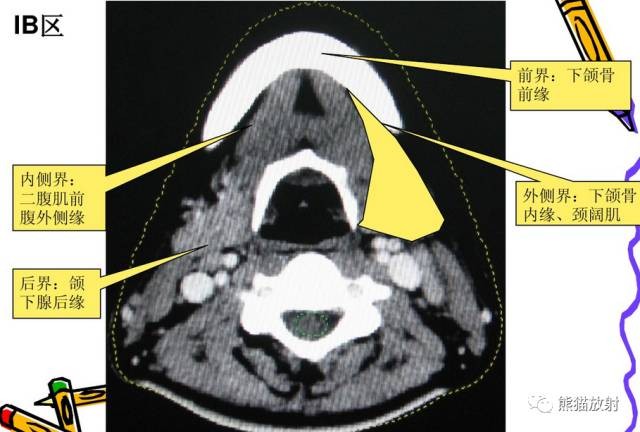

I区:颏下及颌下淋巴结

舌骨上水平CT增强图像

横白线在两侧颌下腺后缘。

线以前为I区淋巴结,线后为II区淋巴结。在颈内静脉附近为IIA区,颈内静脉后面不接近静脉的淋巴结为IIB区。